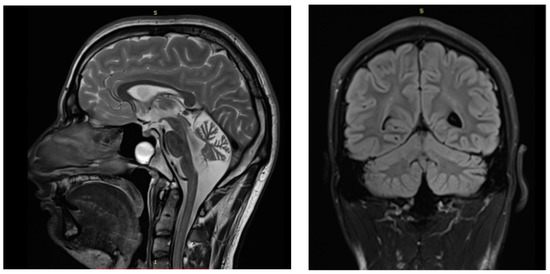

2.1. Clinical Description